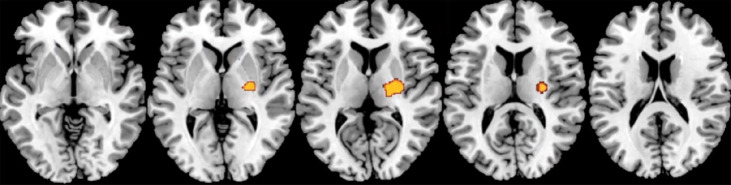

Results: A total of 70 (39 male, 31 female) were analysed, with an average number of occlusal pairs of 10.21 (3.99). According to the Spearman correlation coefficient, a lower number of occlusal pairs was related to a reduction in white matter (right external capsule and posterior limb of the internal capsule), a reduction in grey matter (right temporal superior and medial gyrus and left cerebellum crus 1) and a reduction in thickness of the cerebral cortex (rostral anterior cingulated cortex of the right hemisphere and areas in the right and left hemisphere, especially in the frontal cortex).

Conclusions: The number of occlusal pairs is related to the volume of white matter, grey matter, and thickness of the cerebral cortex in areas of the brain that are directly involved in the onset and progression of Alzheimer's disease and other dementias.